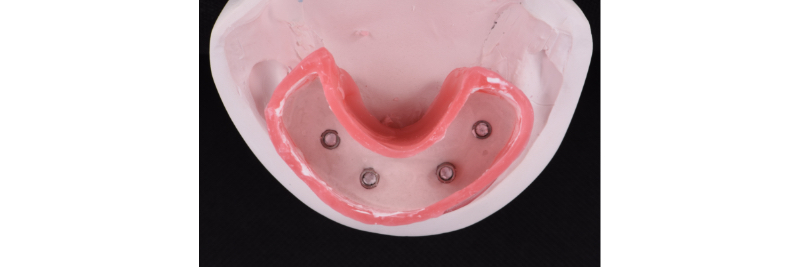

Master cast of four tissue-level analogs with soft tissue moulage.

Intaglio surface of the processed and polished implant hybrid prosthesis.